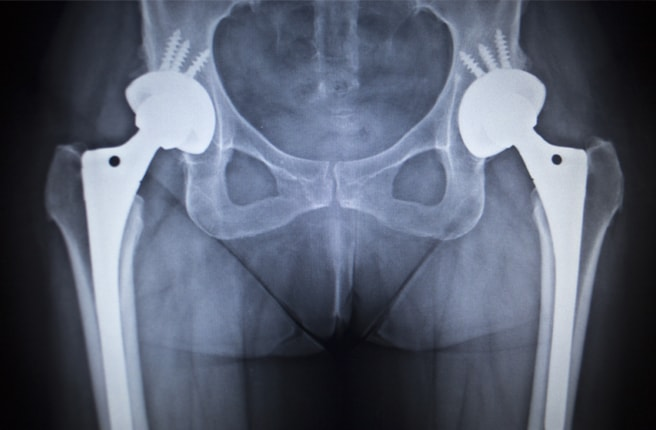

Если болезнь определяется уже на третьей степени, или несмотря на проведенные лечебные действия состояние больного только ухудшилось, возможно применение более серьезных мероприятий. На этой стадии прибегают к оперативным методам. Сустав полностью заменяют на протез. Эндопротезирование на сегодняшний день достаточно распространенный способ избавления от коксартроза.

Протезы приживаются в течении одного или двух месяцев. На то как быстро это произойдет влияют многие факторы, это и возраст пациента, его физическое состояние на момент проведения оперативного вмешательства, правильное выполнение всех рекомендаций врача. Обычно протез возвращает человеку былую подвижность, избавляет от болей, позволяет вести нормальный образ жизни. Стандартный срок службы протеза 15-20 лет.

Фото из свободных источников.